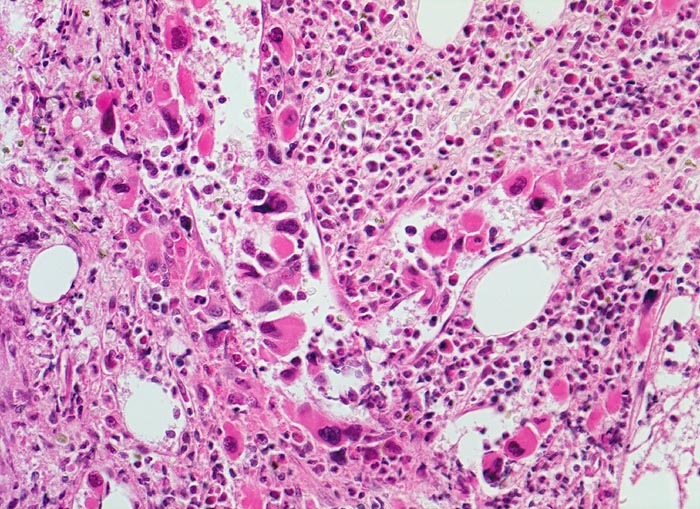

Morphologie

Morphologische Merkmale:

• Osteosklerose: verplumpte und breite Knochenbälkchen.

• Kollagenfibrose.

• Dilatierte Sinusoide mit intrasinusoidaler Blutbildung.

• Vermehrung von atypischen, in Gruppen liegenden Megakaryozyten mit abnorm lobulierten Kernen.

• Nacktkernige (zytoplasmaarme) und vergrösserte Megakaryozyten.

• Hyperplastische ausreifende Myelopoese.

• Hypoplastische Erythropoese.

• Retikulinfaserfibrose des Marks vorhanden aber in der HE Färbung schwierig quantifizierbar.